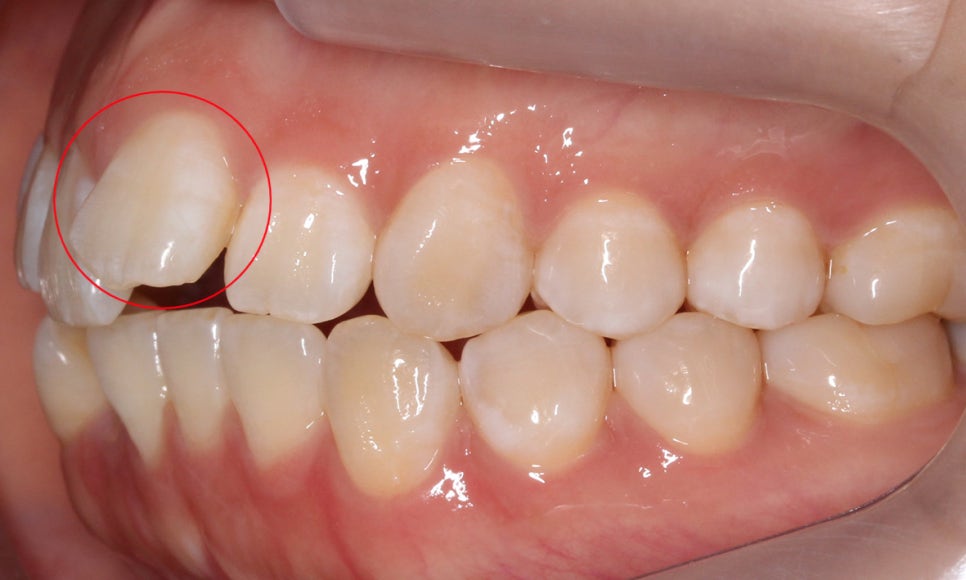

정면 구내사진을 보시면 위와 같이

상악과 하악을 교합하였을 때

전치부의 치아들이 제대로 교합되지 못하는 모습인데요,

상악 전치부의 경우 21번 중절치가 위쪽으로 들려있는 모습으로

덧니라고는 보기 어렵지만 앞니돌출 이 있는 모습입니다.

구치부에서 전치부로 이어지는 좌우의

교합평면을 확인해보면 양쪽 교합평면 모두

전치부의 앞니돌출 증상으로 인해 스마일라인이

가지런하지 못한 것으로 보이는데요,